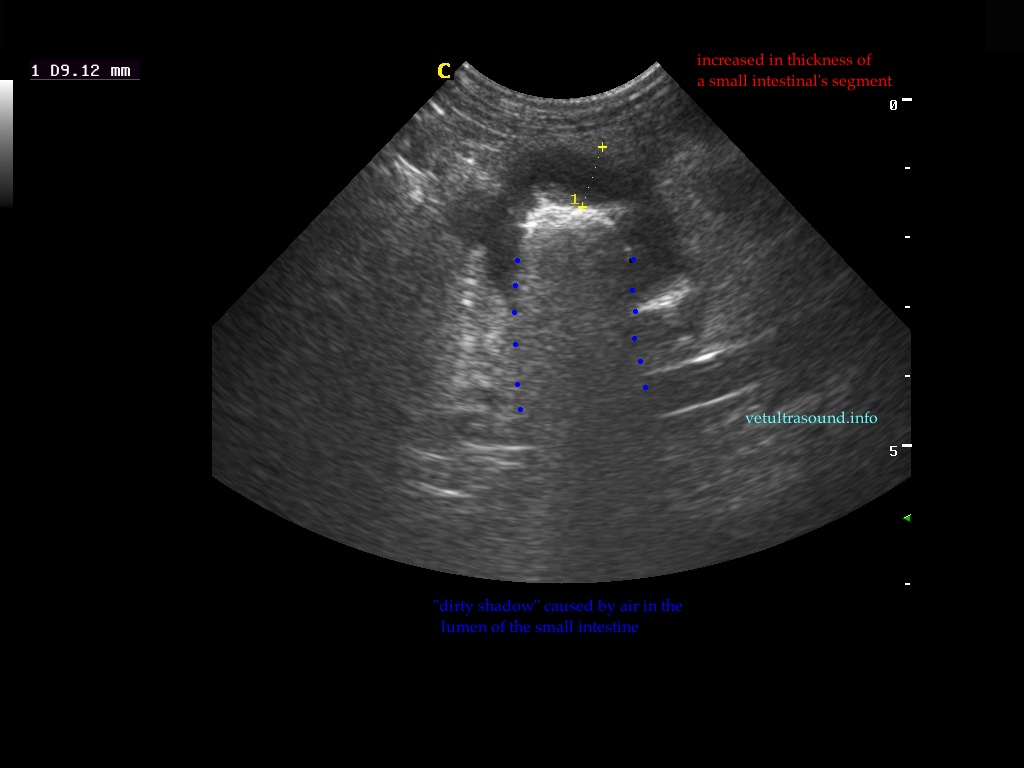

Findings: The ultrasound exam revealed a marked distention of a segment of the small intestine which ended in a narrowed lumen due to a thickened wall. The mesenteric lymph nodes were markendly enlarged and hypoechoic. A fine needle aspirate was performed.

The GIF shows the frames from the normal small intestinal layering to the thickened abnormal wall in a perpendicular view.